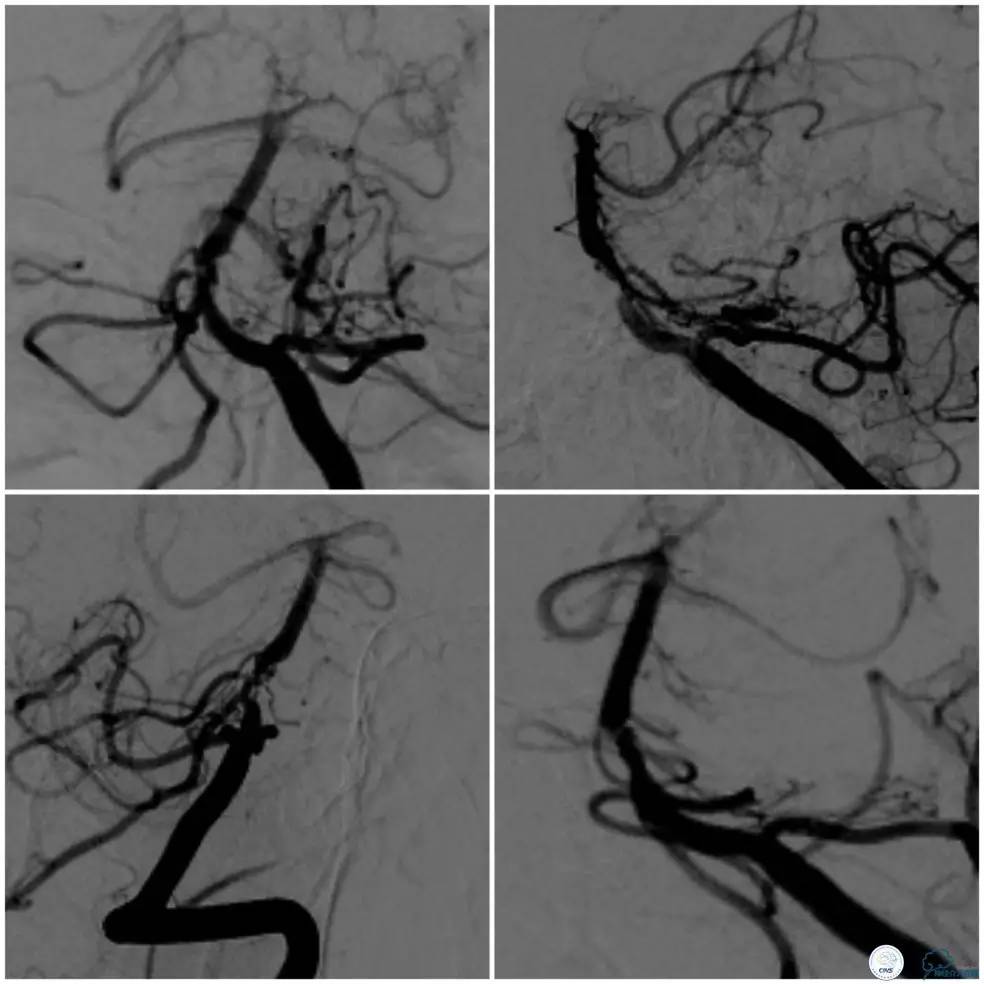

术前造影(图5、6):基底动脉近段狭窄,局部管腔不规则,似有“充盈缺损样改变”,管壁不光滑,前向血流减慢。可见右后交通动脉开放,见双侧大脑后动脉,基底动脉尖和上段显影。

图5

图6